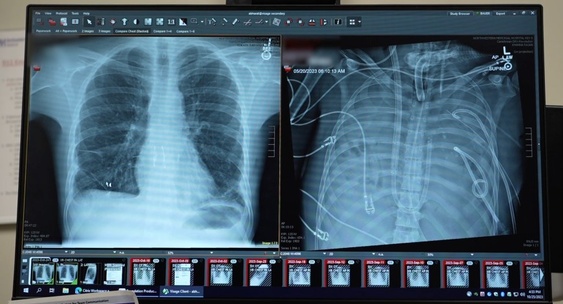

Впервые пациент двое суток прожил без легких в ожидании трансплантации

33-летний пациент пережил 48 часов без собственных легких благодаря новой системе искусственного дыхания, разработанной командой из Медицинской школы Файнберга Северо-Западного университета в Чикаго.Наука

Ключевое отличие — аппарат подключен к сердцу, обеспечивая правильное давление для циркуляции крови и полноценную работу сердца, в отличие от классической ЭКМО, где легкие остаются в теле пациента.Наука